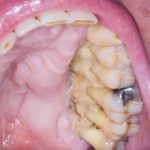

Fig. 3C Caso clinico di MRONJ diffuse in paziente oncologico che ha assunto farmaci anti-riassorbitivi ad alto dosaggio.